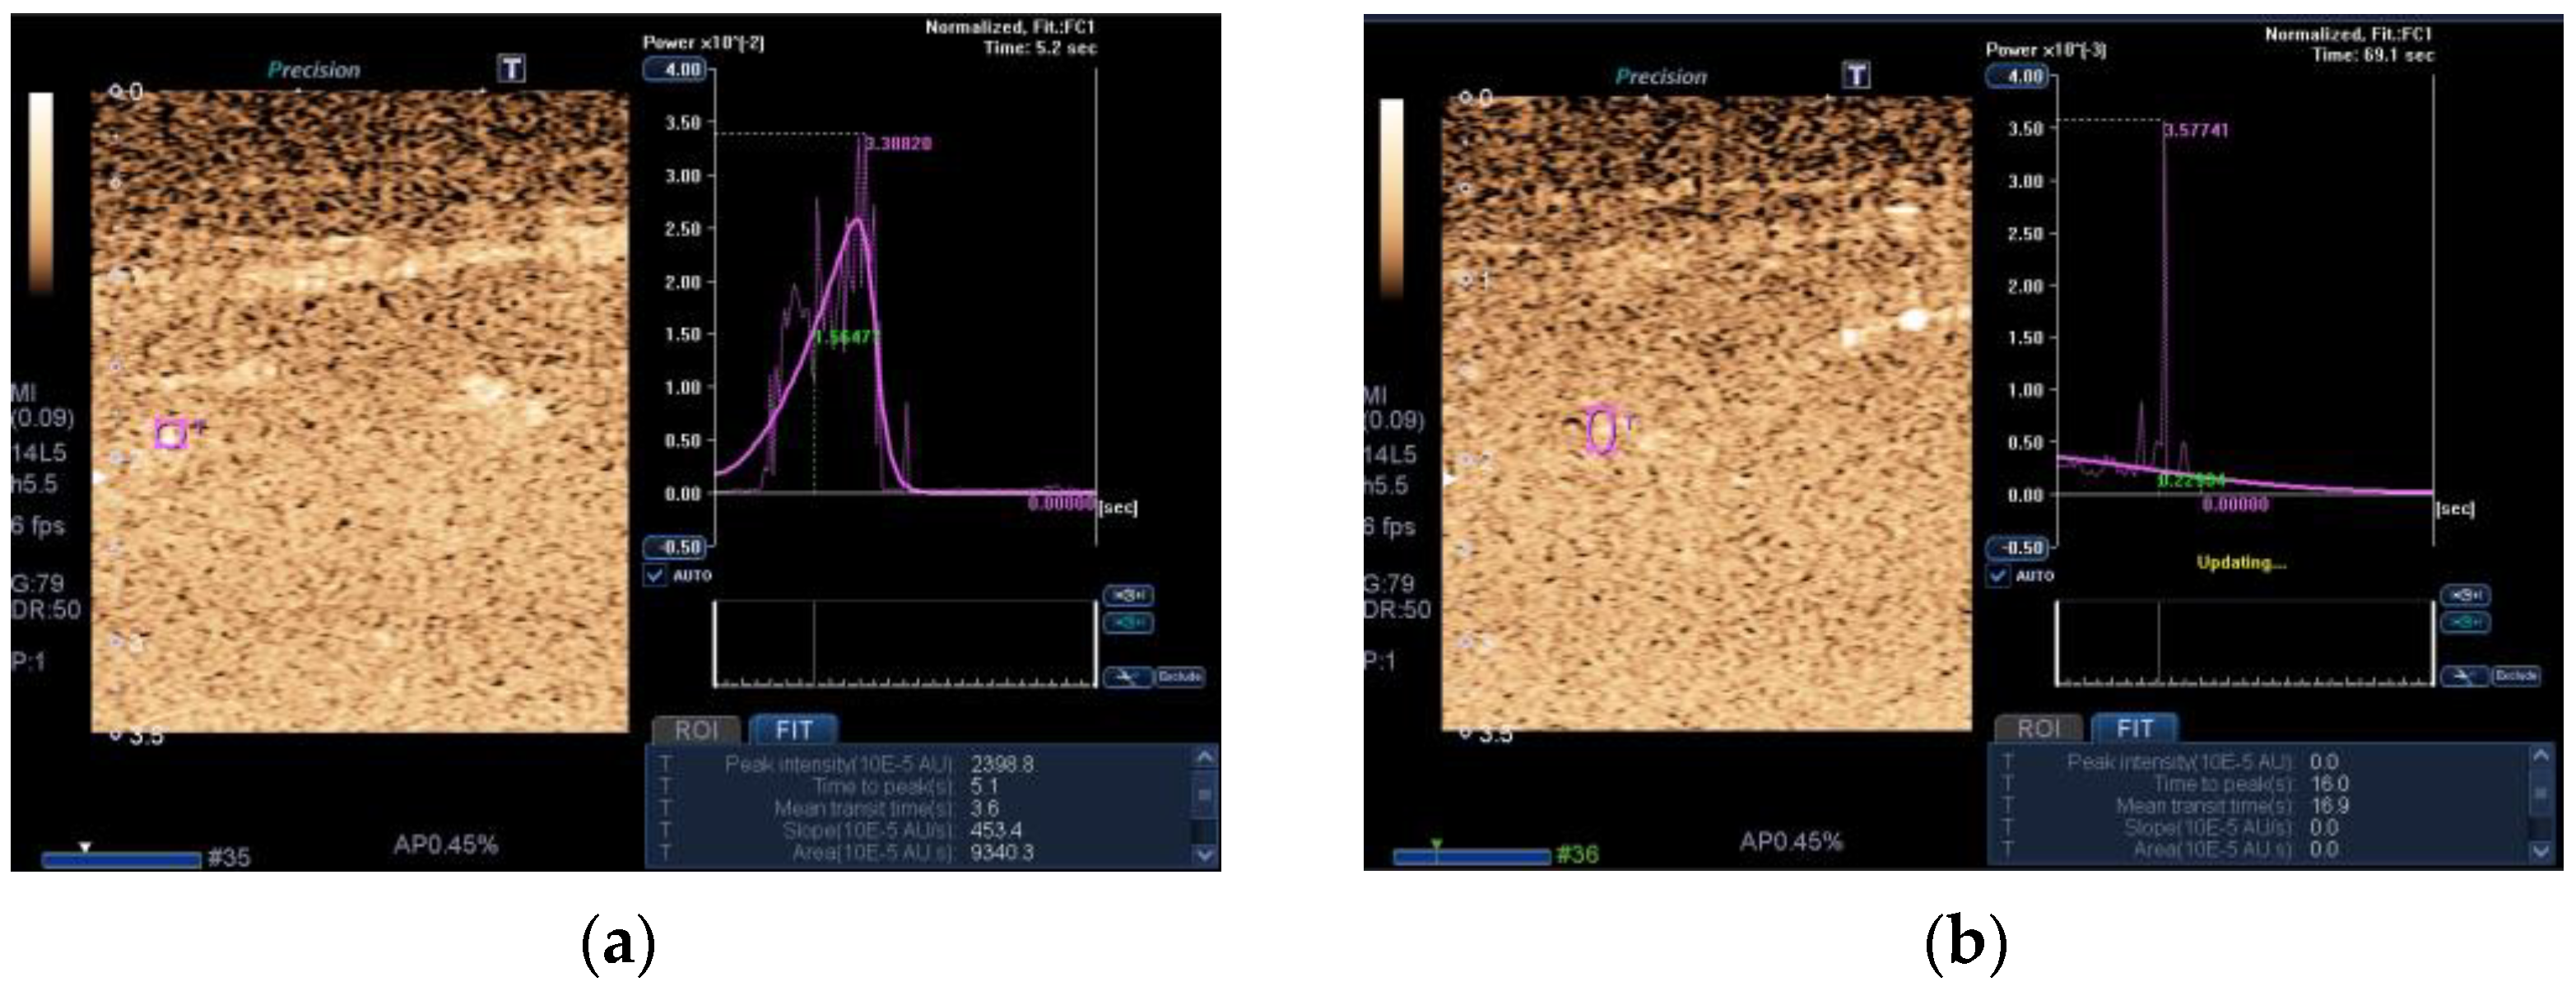

- Hernández-Socorro, C.R.; Saavedra, P.; López-Fernández, J.C.; Lübbe-Vazquez, F.; Ruiz-Santana, S. Novel high-quality sonographic methods to diagnose muscle wasting in long-stay critically ill patients: Shear wave elastography, superb microvascular imaging and contrast-enhanced ultrasound. Nutrients 2021, 13, 2224. [Google Scholar] [CrossRef]